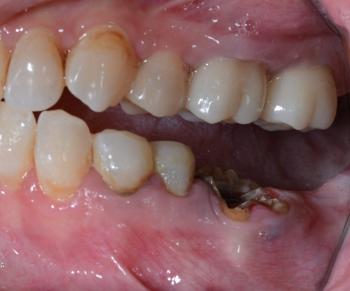

Painful Tooth Misalignment With Fractured Lower Tooth and Secondary Infection Risk

Overall Alignment

Visible malocclusion (misalignment) between upper and lower teeth

Improper bite contact causing uneven force distribution

Signs of traumatic occlusion

Lower Teeth Findings

Fractured lower tooth (partial crown loss)

Exposed dentin with plaque accumulation

Brownish discoloration near fracture margins

Early decay at the broken edge

Gum irritation around damaged tooth

Upper Teeth Findings

Mild crowding

Uneven enamel wear patterns

Occlusal surfaces showing early stress wear

Primary Diagnosis

Malocclusion With Traumatic Bite